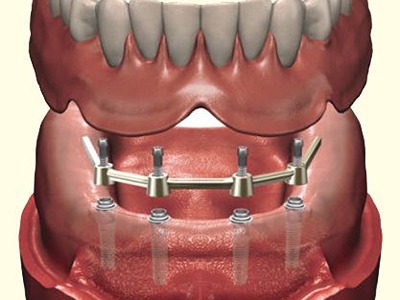

You can rely on us for dependable, comfortable, and expert dental care. With advanced technology, experienced specialists, and personalized treatment plans, we ensure every patient receives trusted, effective solutions for long-term oral health and confident smiles.

Dr Nitesh Rai, specializes in replacement of teeth with complete dentures, removable partial dentures, fixed partial dentures and Implants.

He has been actively involved in providing implant treatment for over two decades. He is also a committed academician, educating dental students and has been associated with Krishnadevaraya college of Dental sciences, Bengaluru as a Senior Professor, PG Guide and teacher in the Department of Prosthodontics, Crown and Bridge and Implant.